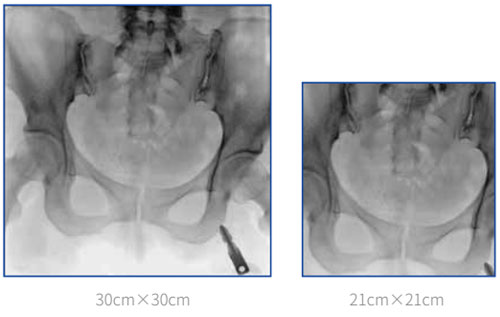

Entire pelvic imaging

lmage taken by 30cm x 30cm FPD can basicly cover the entire pelvic floor. In the surgery of bilateral-pevic fractures or pelvic ring internal fixation, all the fracture sites can be revealed by single exposure, which significantly improves overall efficiency.

lmage taken by 30cm x 30cm FPD can basicly cover the entire pelvic floor. In the surgery of bilateral-pevic fractures or pelvic ring internal fixation, all the fracture sites can be revealed by single exposure, which significantly improves overall efficiency. |